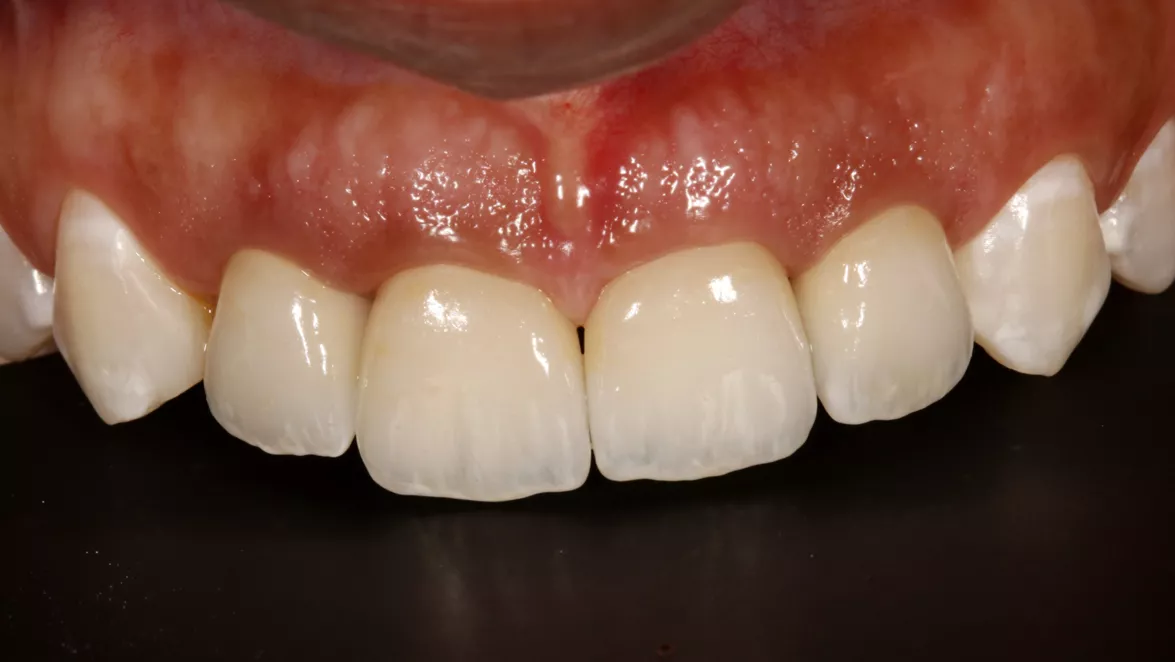

Guided rehabilitation with implant in upper incisors region, after loss due to root resorption